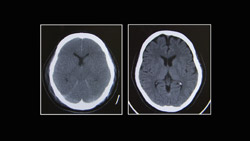

6月5日に全国で公開された映画「孤高のメス」。舞台は1980年代、当時の法律では認められていなかった脳死での臓器移植がテーマです。「あの子の手は、あんなに温かいのに…。」交通事故で脳死状態に陥った息子を前に、母親は戸惑いながらも脳死下での臓器提供を決断します。

7月に施行された改正臓器移植法では、本人の意思がわからなくても、家族が承諾すれば脳死状態でも臓器提供が可能になります。突然降りかかった深い悲しみの中、臓器提供の決断を下す家族の心の負担は計り知れません。